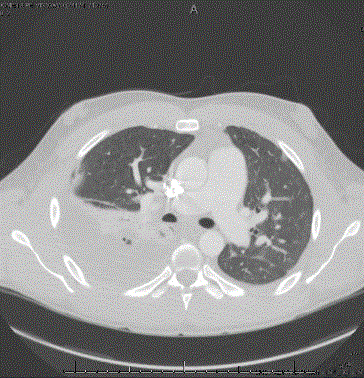

In the ER his vital signs were significant for fever to 40.1 C, tachycardia, tachypnea, and hypoxia requiring 3L oxygen. Physical exam revealed significant diaphoresis and decreased breath sounds at the right base. He had dullness to percussion over the right lower lung field, but no egophany was noted. A chest X-Ray showed possible right pleural effusion with no consolidation (Figure 1). CTA was obtained and showed no pulmonary emboli but found right air space concerning for pneumonia and an abscess superior to his right lower lobe bronchus. Blood cultures were obtained, he was given fluids and started on Ceftriaxone and Azithromycin (Figure 2).

Figure 2. CTA